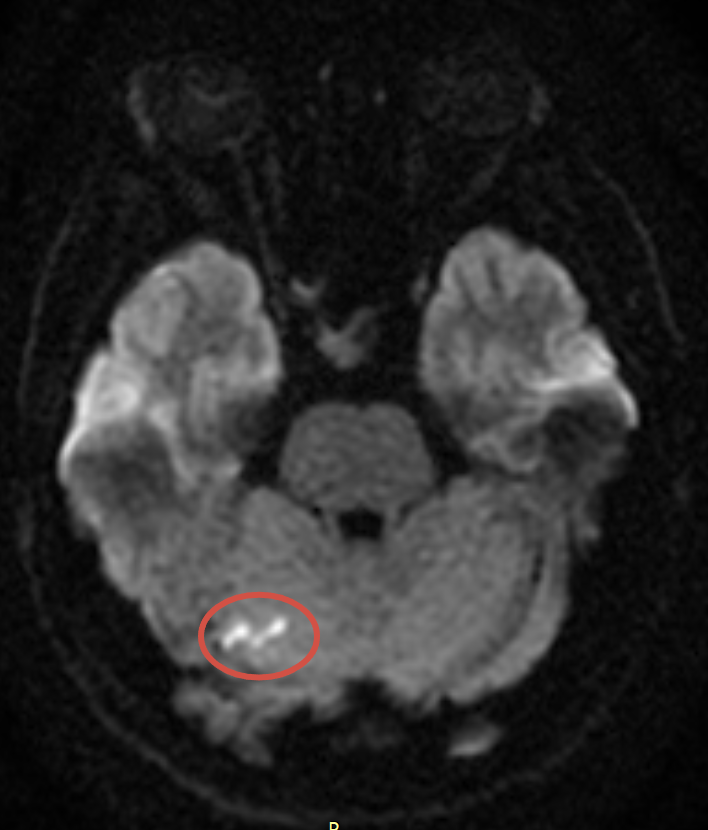

В отделение экстренной помощи поступил пациент 40 лет. Накануне он выполнял физическую нагрузку, после чего прилёг на кровать. При попытке встать с кровати внезапно возникли звон в ушах, головокружение, боль в области шеи, тошнота, рвота и расфокусировка зрения. Со временем жалобы постепенно регрессировали.

При проведении магнитно-резонансной томографии головного мозга выявлены множественные очаги острого ишемического инфаркта в вертебро-базилярном бассейне с обеих сторон.